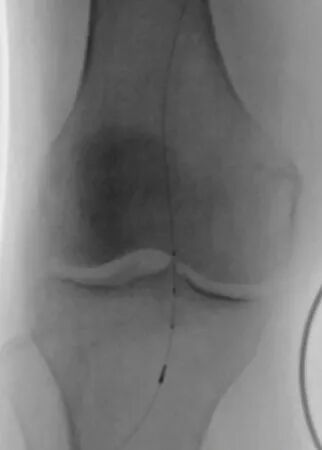

第一个病例中,患者因下肢严重缺血入院。术前常规血管造影提示为“动脉闭塞”。如果按照传统思路,需要直接实施球囊扩张加支架植入手术。为实现精准诊疗,血管外科团队决定启用IVUS进行血管腔内探查。

IVUS探头进入血管后,病变真相清晰呈现。血管内并非预想的慢性动脉硬化斑块,而是大块脱落的血栓堵塞了血管。患者属于急性或亚急性栓塞,与慢性闭塞的治疗方案截然不同,原本的支架方案必须推翻。